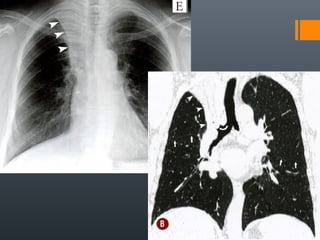

O documento discute vários conceitos radiológicos incluindo consolidação, atelectasia, nódulos, pseudocavidades e padrões intersticiais, fornecendo definições, sinais e diagnósticos diferenciais para cada tópico. Ele também discute a redução da atenuação pulmonar e fornece um link para mais informações.